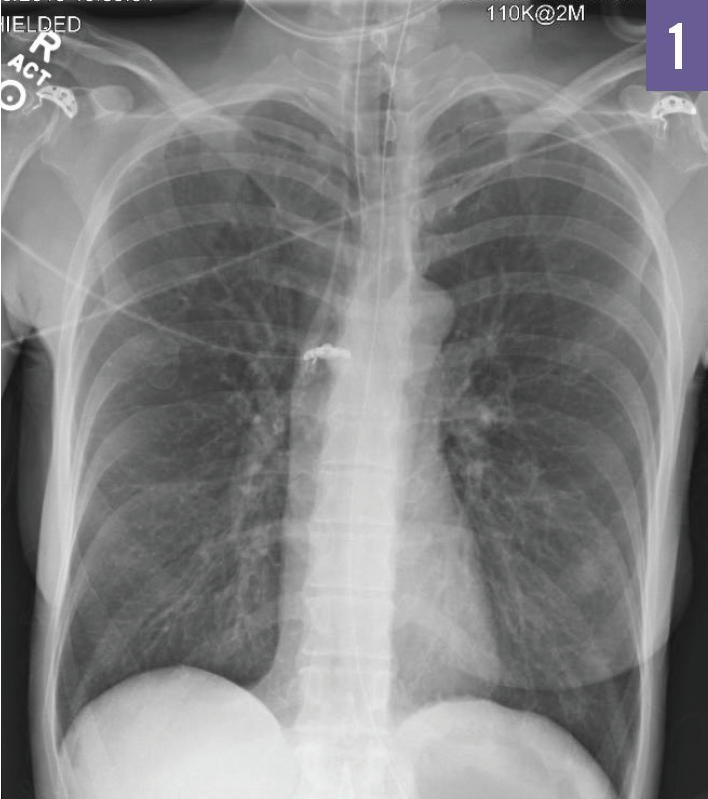

In August 2015, a 51-year-old woman presented to the emergency department after having been evaluated by her primary care physician.